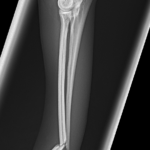

橈骨固定術 #249 Toy Poodleさんがソファーからジャンプして橈骨骨折をしたとのことで主治医の先生から固定術の依頼がありました。1.5 Titanium Locking Plateで固定術を行いました。しばらくは安静が必要です。 症例カテゴリー 放射線治療整形外科軟部組織外科脳神経外科内科腫瘍外科救急・集中治療リハビリテーション科腫瘍内科内視鏡科脳神経科呼吸器外科中医・漢方猫の腎移植循環器科